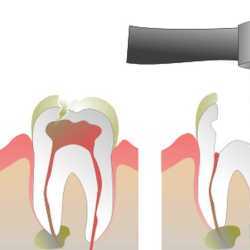

Inicio Especialidades Endodontia